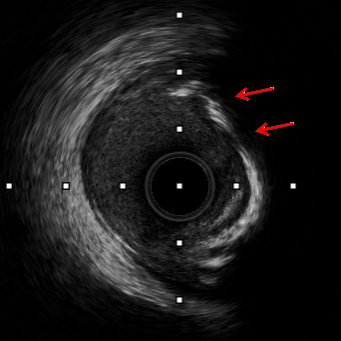

术后

钙化环断裂

Shockwave球囊冲击波治疗后,顺利植入支架